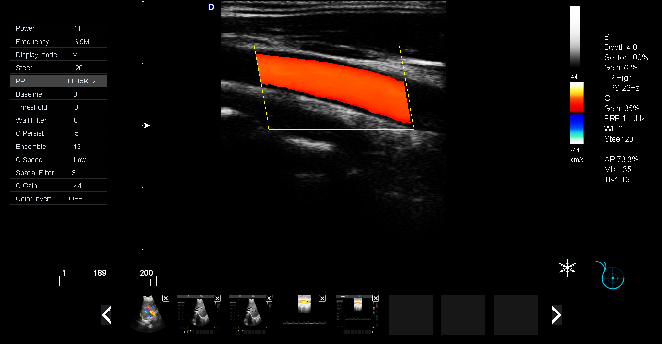

P5-VET便攜獸用彩超機頸動脈檢查圖

頸動脈血流:

頸動脈彩超是診斷、評估頸動脈壁病變的有效手段之一,在動脈粥樣硬化的流行病學調查和對動脈粥樣硬化預防、治療試驗的有效性評價中起著關鍵作用。

頸動脈彩超不僅能清晰顯示血管內中膜是否增厚、有無斑塊形成、斑塊形成的部位、大小、是否有血管狹窄及狹窄程度、有無閉塞等詳細情況, 并能進行準確的測量及定位,還能對檢測動脈的血流動力學結果進行分析。